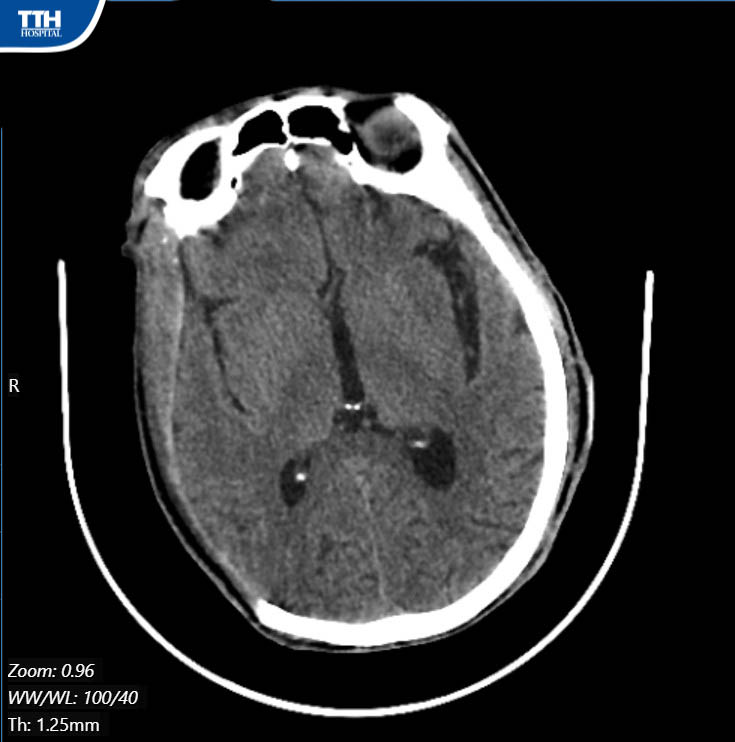

Sau khi hội chẩn, các Bác sĩ khoa CT – YHTT quyết định phẫu thuật vole sọ lấy máu tụ, giải tỏa não. Kíp mổ do BSCKI Phan Duy Đán – Phẫu thuật viên khoa CT – YHTT cùng ekip thực hiện. Ca phẫu thuật kéo dài gần 2 tiếng căng thẳng đã diễn ra suôn sẻ, thuận lợi. Sau 1 tuần theo dõi, điều trị tích cực, sức khỏe bệnh nhân đã hồi phục nhiều, hiện bệnh nhân tỉnh táo, hết liệt tay chân, vết mổ ổn ổn định và có thể xuất viện trong vài ngày tới.